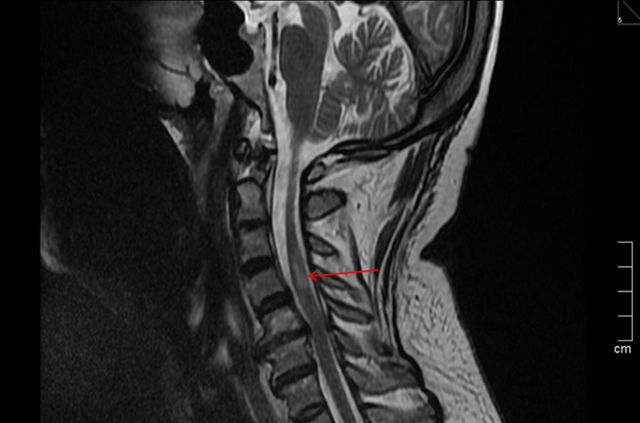

Как выглядит спинальный ишемический инсульт на МРТ

- КТ или МРТ позвоночника, чтобы определить повреждения или смещения позвонков, наличие/отсутствие остеофитов либо осколков, сужена ли межпозвонковая щель или нет. Визуальный метод помогает обнаружить компрессию позвоночного канала, спинальные опухоли, гематомы или межпозвоночные грыжи